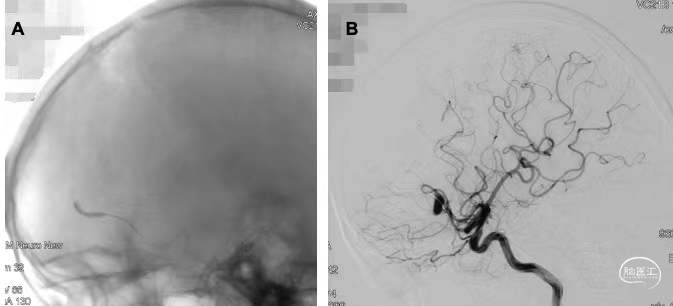

遂择期行颅内多发动脉瘤切除术。取右额颞弧形切口,常规开颅,打开约5×6cm骨窗,悬吊硬膜后放射状剪开。首先行大脑中动脉动脉瘤切除术,导航下定位动脉瘤位置,在大脑中动脉动脉瘤脑表面投影处进行右额叶皮层造瘘,向下约0.5cm可见动脉瘤,呈梭形,动脉瘤夹夹闭其近端动脉,电灼两端载瘤动脉后完全切除动脉瘤。再行大脑前动脉动脉瘤切除术,沿纵裂向深部分离右额叶及大脑镰,向下约2cm可见动脉瘤,呈梭形,动脉瘤夹夹闭其近端及远端动脉,电灼两端载瘤动脉后完全切除动脉瘤(图4)。标本送病理,术中回纳骨瓣。术后患者恢复满意,体格检查无新发神经功能缺损。

图4. 术中镜下所示 4a右额叶皮层造瘘暴露右侧大脑中动脉动脉瘤(绿圈),左侧为额叶,右侧为颞叶;4b夹闭梭形动脉瘤近端动脉后电凝载瘤动脉;4c沿纵裂向下分离暴露右侧大脑前动脉动脉瘤(绿圈),上为额侧,下为枕侧;4d夹闭梭形动脉瘤载瘤动脉。